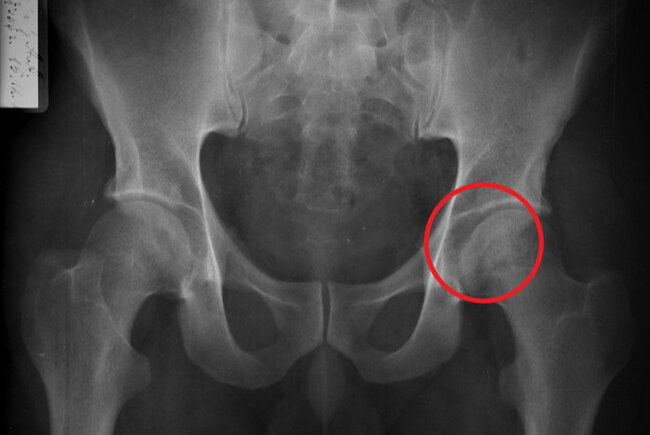

Ортопед был первым врачом кто, более-менее серьезно отнеся к ситуации. Выслушал меня, провел осмотр, в ходе которого выявил что левая нога стала короче правой на 2-3мм, так же он замерил радиус вращения тазобедренного сустава, угол сгибания коленного сустава. После этих манипуляций у меня появилось доверие к нему. Это было первый раз, когда был озвучен диагноз коксартроз. Но для его подтверждения он меня направил на рентген. По коленному суставу у ортопеда было предположение что это отдается боль от тазобедренного сустава. Но у нас в поликлинике толи была очередь на него, то ли он был сломан. И тогда я не нашел ничего лучше, кроме как поехать к тете в хирургию в соседний город, 35 км от Самары делать рентген, поскольку мне уже не хотелось терять ни минуты на обследования, хотелось начать нормальное лечение, ведь я попал к хорошему врачу. Тетя у меня санитарка в хирургическом отделении районной больницы, человек добрейший и рассудительный, пока сидели с ней в коридоре и ждали рентгенолога по человечески поговорили с ней, сказала что таких как я пруд пруди, у нее у самой суставы тоже болят, сидит на уколах да на мази, это не страшно, жить можно, хотя сказала что такие проблемы у людей в предпенсионном возрасте и старше, а тут я – молодой, может у меня что то другое. Однако рентген, хоть и аппарат там древний, все-таки показал дегенеративные изменения в головке бедра: